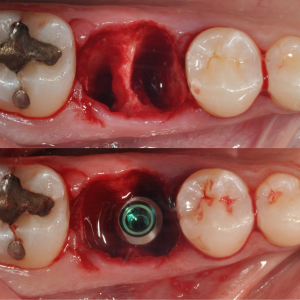

From A to Z Master Hands-On Course for No crestal bone loss